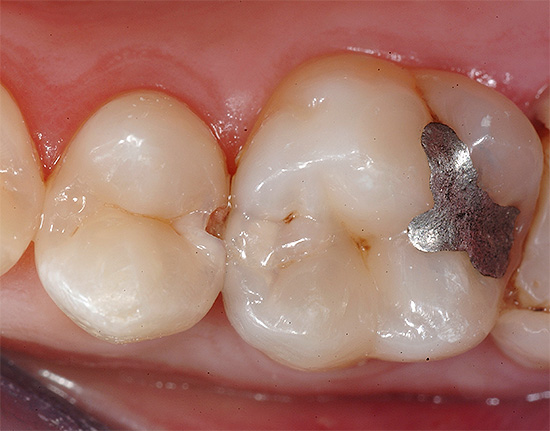

Um tipo obsoleto de material de enchimento são as amálgamas (prata e cobre). Não podem ser utilizados nos dentes da frente, por não serem estéticos, portanto a área de uso é nas classes Black 1, 2 e 5, bem como nos dentes cobertos com coroas.

Para o tratamento de cárie profunda no século XX, as amálgamas eram um material de enchimento indispensável que ainda é encontrado. Praticamente não há obturações, exceto amálgama, que possui uma existência segura de 20 a 30 anos no dente. O amálgama de prata é um selo metálico com um efeito antibacteriano ativo da prata (e mercúrio). As possibilidades de sua retenção são quase infinitas.

Um tipo mais moderno de materiais de envase é o chamado cimento de ionômero de vidro (SIC). Na maioria das vezes, o SIC é usado no tratamento de cárie profunda como material de revestimento para restaurações ou restaurações de compósitos, quase todas as classes negras (tudo depende da classe do material), para preenchimento de todas as classes de dentes de leite, fissuras de vedação, coroas de fixação etc.

As clínicas modernas dão preferência a materiais de cura por luz funcionais e estéticos que se provaram no tratamento de cáries profundas. Eles são colocados em cavidades cariosas de qualquer classe, de uso conveniente, fácil e firmemente presos aos tecidos dos dentes e bastante duráveis com a execução exata dos detalhes técnicos da produção.